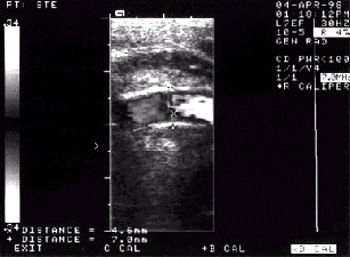

Исследование проводят в В-режиме. Толщину слоя “интима–медиа” (ТИМ) измеряют на уровне общей сонной артерии (СА) и ее бифуркации (рис. 4.36). В норме ТИМ не превышает 1,0 мм (рис. 4.36, а). ТИМ от 1,0 до 1,3 мм расценивают как утолщение стенки артерии, а значения этого показателя, превышающие 1,3 мм, — как ультразвуковой признак атеросклеротической бляшки (рис. 4.36, б). Диагноз атеросклероза считают достоверным при обнаружении утолщения стенки артерии или/и наличии фиброзной бляшки.

| Рис. 4.36. Определение толщины слоя «интима–медиа» (ТИМ) при ультразвуковом исследовании сонных артерий. а — норма: ТИМ не превышает 1,0 мм; б — атеросклеротические изменения артерий: выявляются утолщение стенки сонной артерии (ТИМ от 1,0 до 1,3 мм) и атеросклеротическая бляшка в области внутренней сонной артерии (ТИМ больше 1,3 мм). СА — сонная артерия; НСА — наружная СА; ВСА — внутренняя СА |